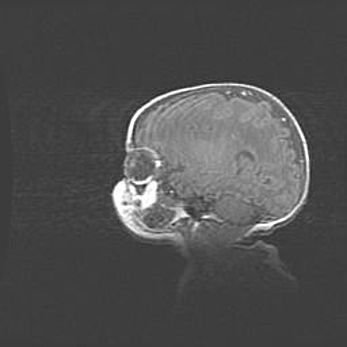

Неполная лизэнцефалия (пахигирия). Открытая гидроцефалия.

Возраст: 17 дней

Вес: 3110 г

Пол: мужской

Окружность головы: 33,5 см

Срок гестации: 35-36 недель

Лизэнцефалия—недоразвитие корковой пластинки и мозговых извилин в результате нарушения миграции нейронов коры. Поверхность мозговых полушарий гладкая. Микроскопически выявляется отсутствие нормальных слоев коры и скопление групп нейронов в подкорковом белом веществе.

Пахигирия—уменьшение числа вторичных извилин. В пораженном полушарии нервные клетки образуют толстый недифференцированный слой с неправильно расположенными нервными волокнами и группами гетеротопных клеток. Нервные клетки незрелые. Белое вещество истончено. При этом нередко аномально развит корково-спинномозговой путь.